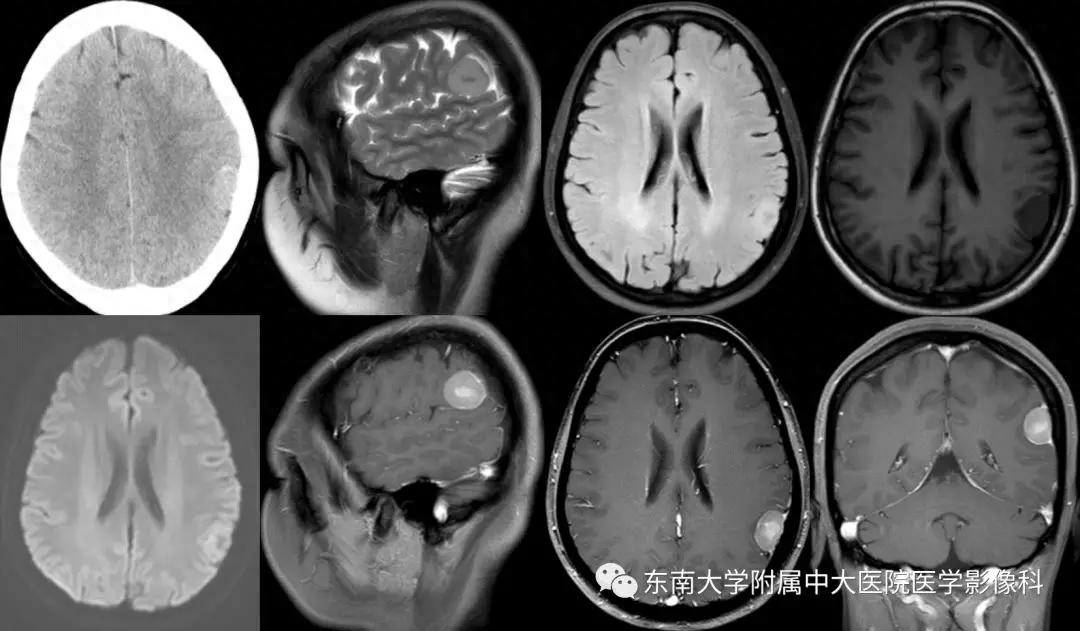

病例1

病史

女,42岁,因“体检发现左顶部占位3月”入院。

影像学表现

CT平扫&MR平扫+增强